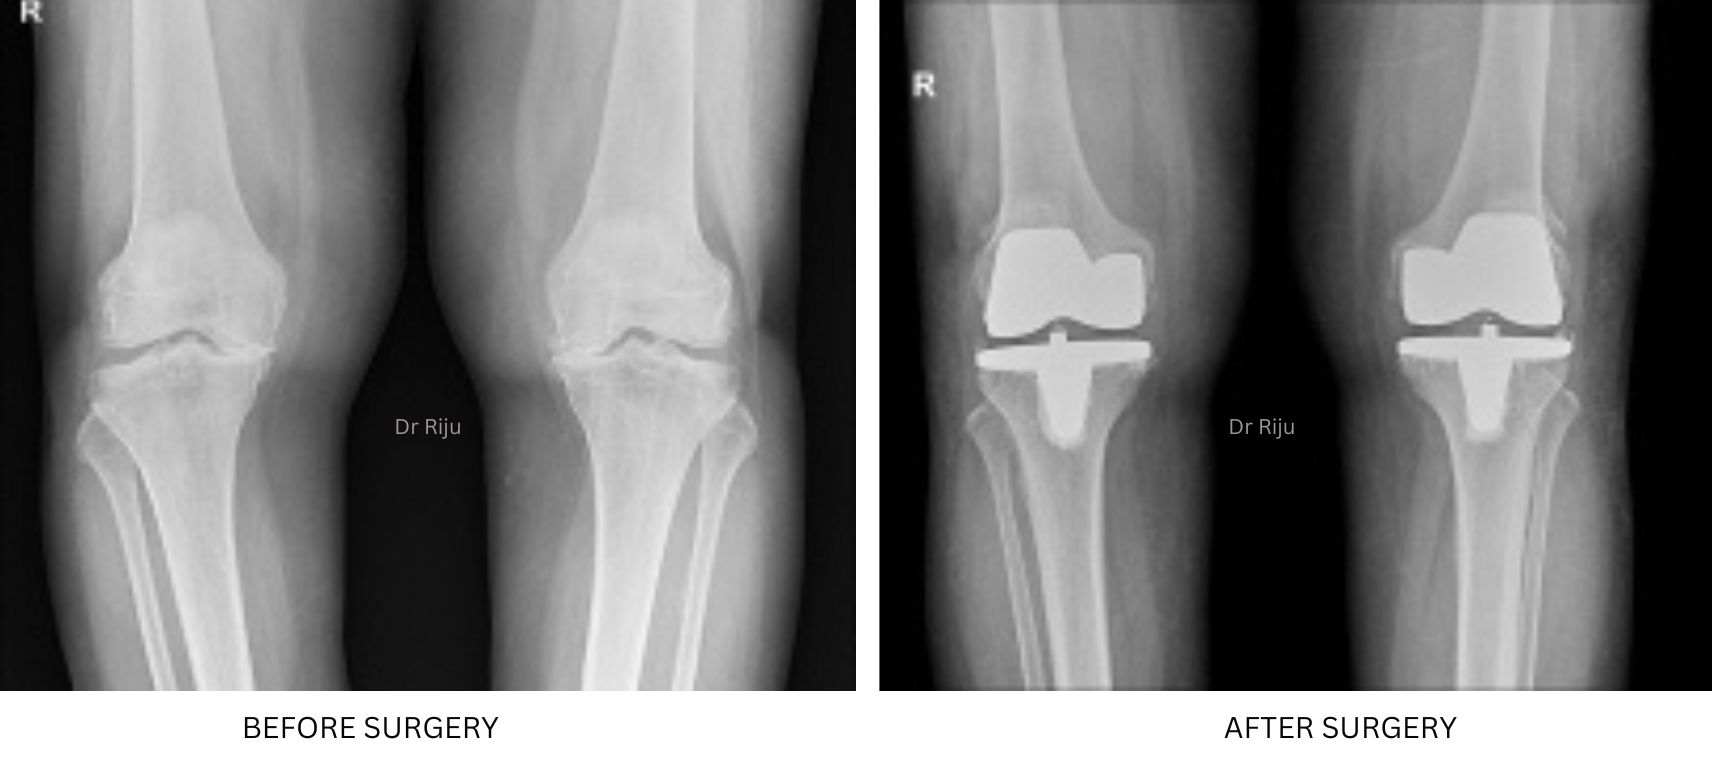

Image Gallery